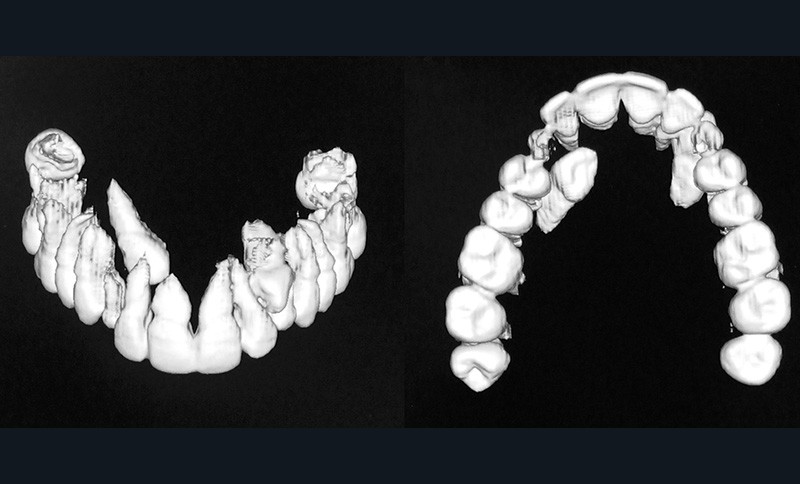

Aline se présente à la consultation pour une demande esthétique concernant ses deux canines lactéales qu’elle trouve trop petites et trop blanches (fig. 1a). Elle présente une classe II squelettique légère sur un schéma méso-divergent. D’un point de vue dentaire, une supraclusion est associée à une classe II d’Angle complète à gauche et de 4 mm à droite. Les canines maxillaires sont incluses (une vestibulaire et une palatine), avec persistance de leurs dents lactéales sur l’arcade (fig. 1b-h).

Traitement multi-attaches et contention

Un protocole orthodontico-chirurgical avec avancée mandibulaire est envisagé pour assurer un bon soutien labial, mais cette option est refusée par la patiente qui craint un visage trop carré. Concernant l’inclusion des canines maxillaires définitives, plusieurs thérapeutiques sont envisageables : 53, 63, 13, 23, ou 53, 63, 14, 24 peuvent être extraites, avec pour conséquence une classe II thérapeutique au niveau des molaires en fin de traitement. Cependant, la patiente souhaite mettre en place ses canines incluses pour conserver tout son capital dentaire et rétablir un idéal fonctionnel et esthétique au niveau des dents antérieures (fig. 2).